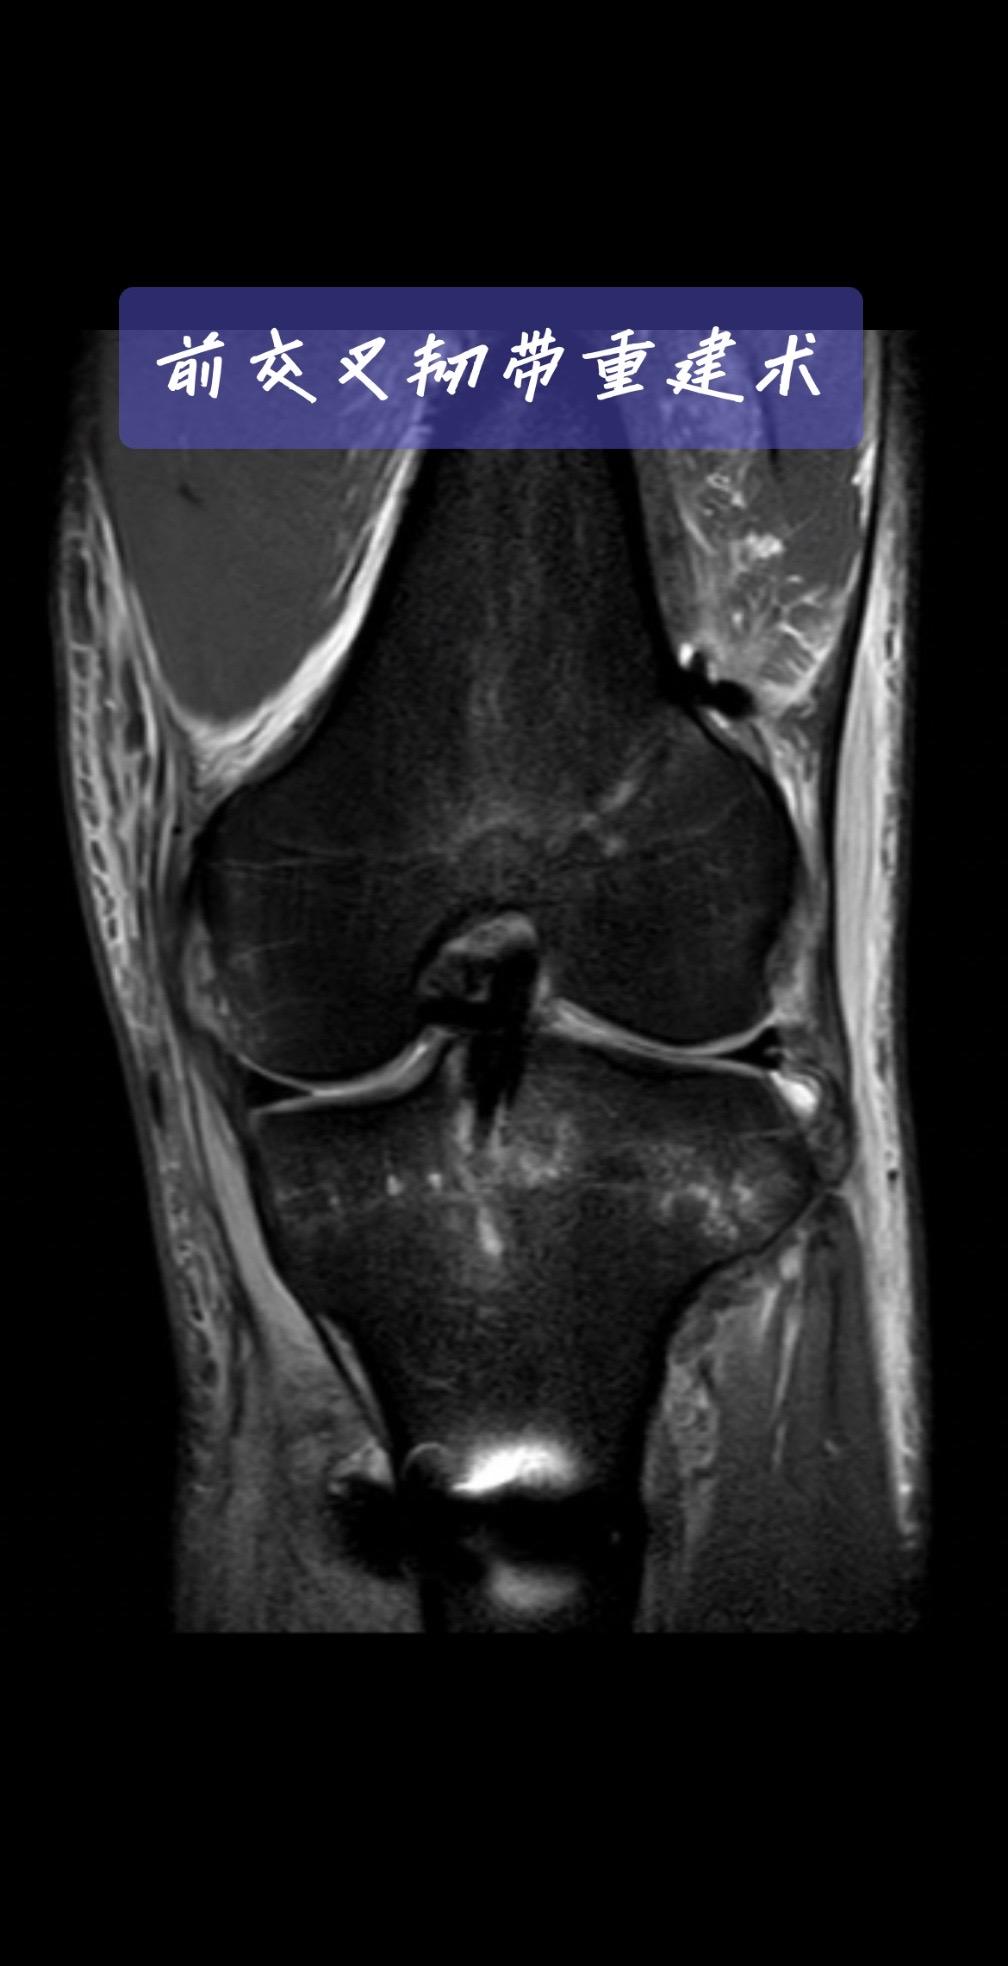

前交叉韧带重建。一台成功的前交叉韧带重建,关键在于“精准”二字。术后CT、MRI复查,就是我们医生的“成绩单”。前交叉韧带重建 运动医学 膝关节术后 骨科医生 医学科普